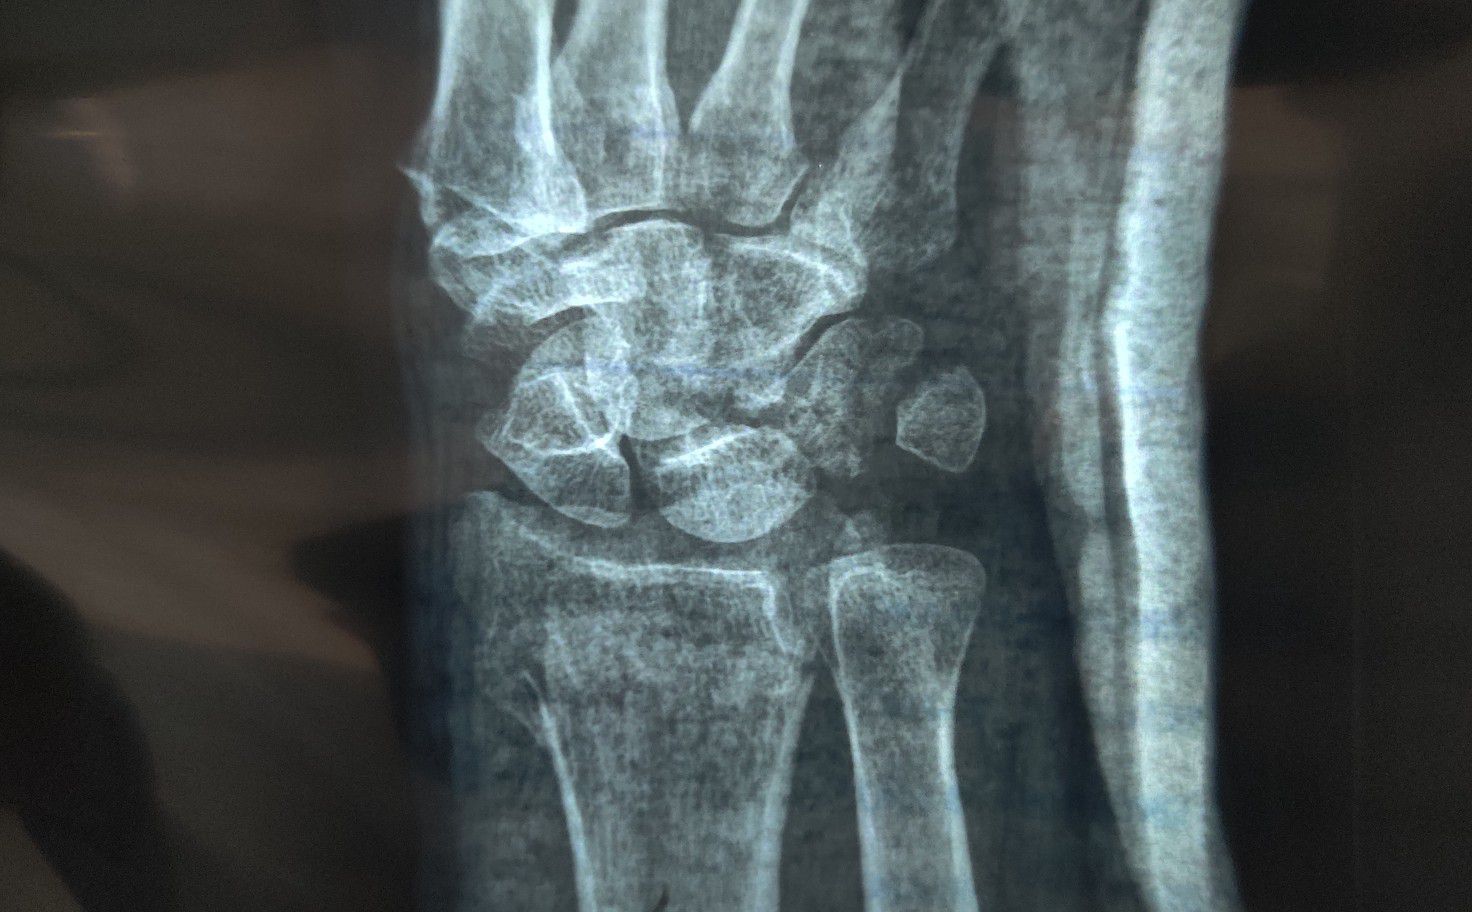

Fracture of Radius and Triquetrum

Radius

Triquetrum